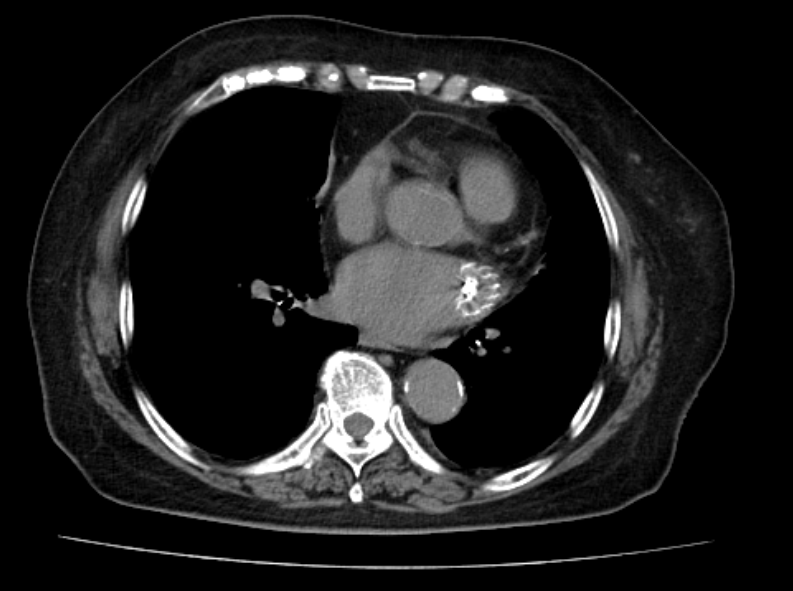

左心耳ct增强

左心耳ct三维重建:评估指南与注意事项

左心耳封堵术后ct表现